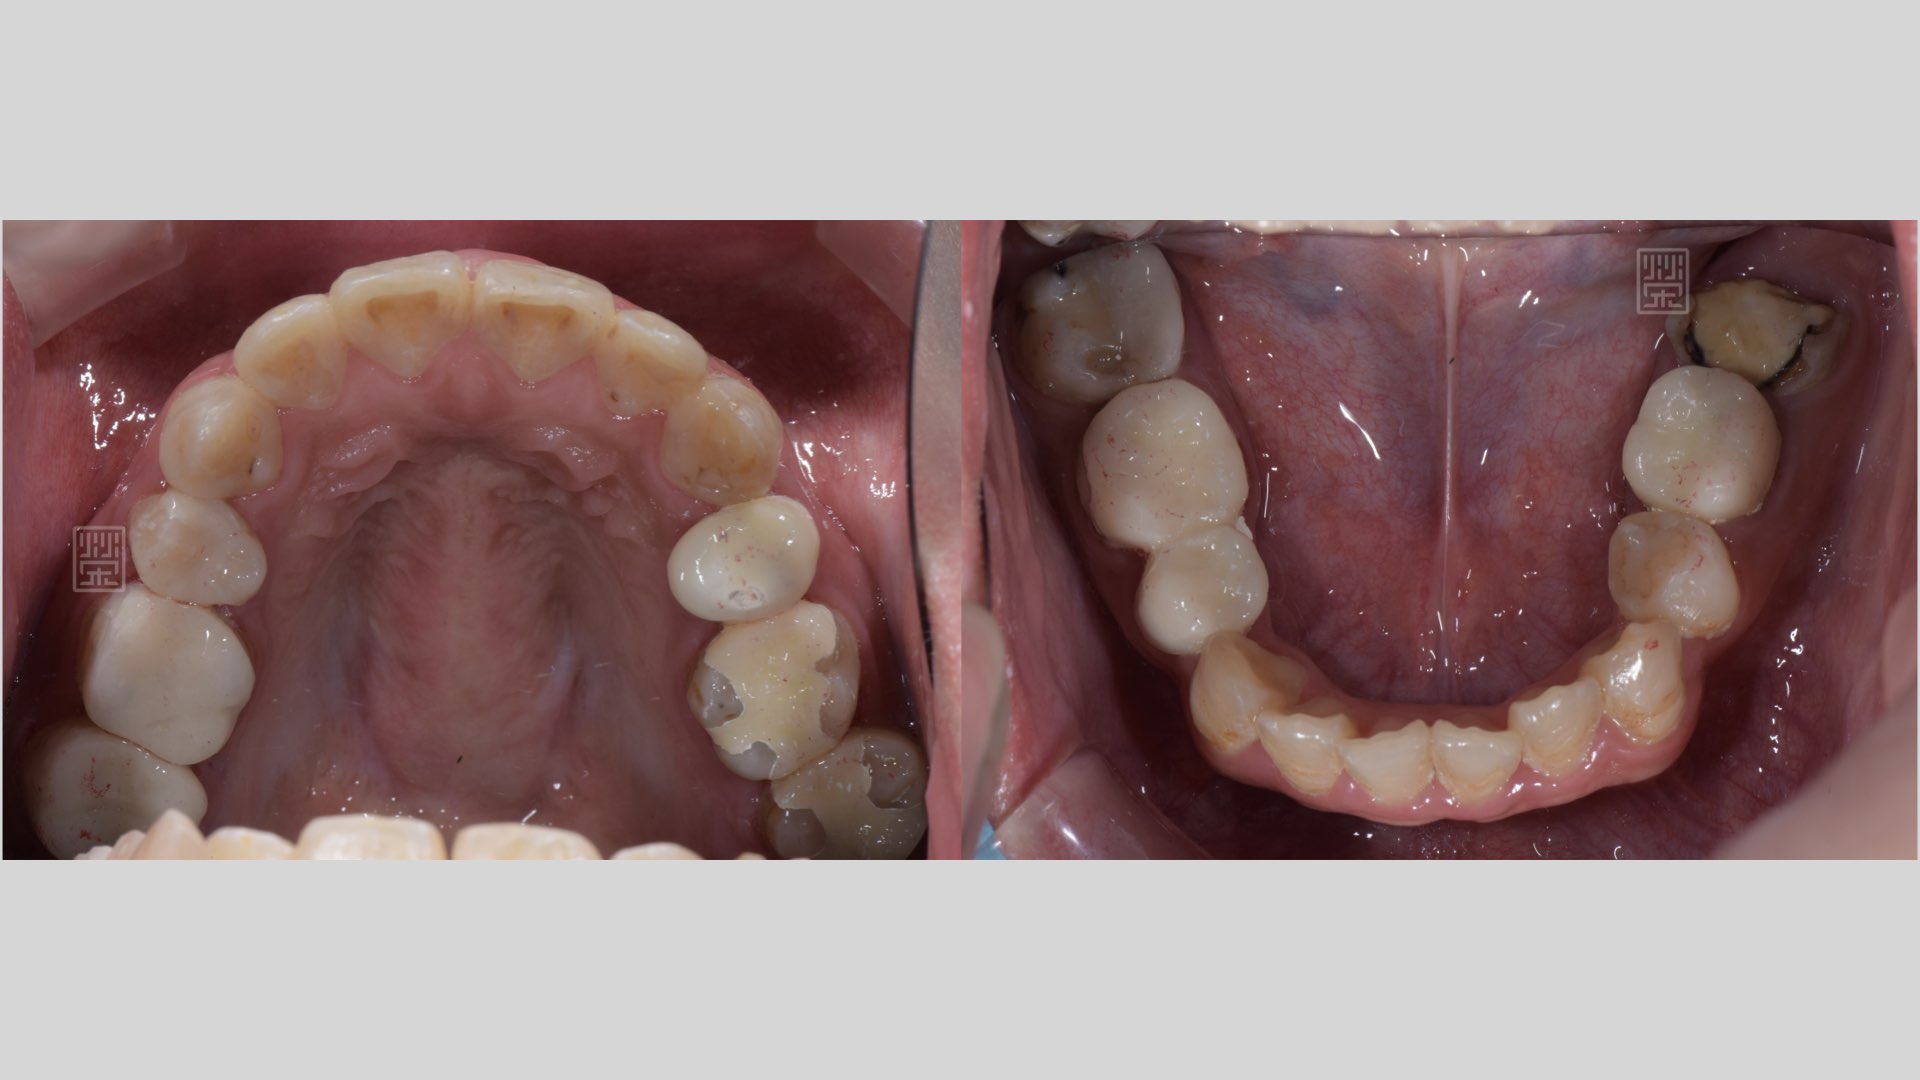

後牙蛀牙清除

後牙蛀牙清除後,牙髓受感染,MTA覆髓治療

後牙多次蛀牙填補